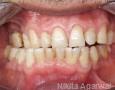

Pictures

Baseline